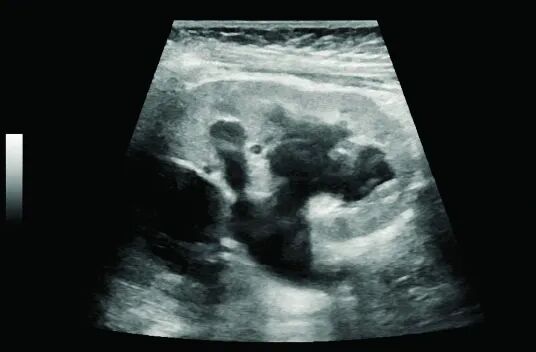

肾结石与肾积水

肾结石在超声下表现为强回声光团,后方伴有声影。超声不仅能发现结石,还能判断其大小、位置以及是否引起肾积水。